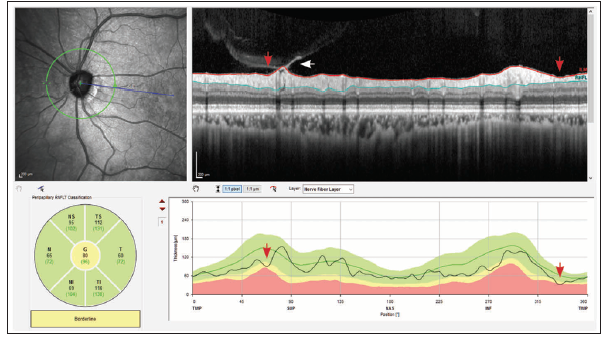

<p>Figure 1. In Case No. 1, the confocal scanning laser ophthalmoscopy infrared fundus image showed an extensive RNFL wedge defect (white arrows). RNFL thinning was seen in the TI sector, and BMO-MRW analysis showed thinning in this region (red arrows). The OCT-derived BMO-MRW measurements confirmed clinically observed rim loss and suggested extensive ONH damage. The posterior pole asymmetry analysis showed significant total retinal thinning representative of arcuate RNFL loss (red outline), extending to the macular area as indicated by the red curves in the total retinal thickness color map.</p>

Figure 1. In Case No. 1, the confocal scanning laser ophthalmoscopy infrared fundus image showed an extensive RNFL wedge defect (white arrows). RNFL thinning was seen in the TI sector, and BMO-MRW analysis showed thinning in this region (red arrows). The OCT-derived BMO-MRW measurements confirmed clinically observed rim loss and suggested extensive ONH damage. The posterior pole asymmetry analysis showed significant total retinal thinning representative of arcuate RNFL loss (red outline), extending to the macular area as indicated by the red curves in the total retinal thickness color map.

A 63-year-old woman with primary open-angle glaucoma presented with a flame-shaped optic disc hemorrhage in the temporal inferior region of her left eye (Figure 1). Although the optic disc showed some rim thinning and an adjacent disc hemorrhage, subjective assessment of the photograph did not fully convey the extent of the neuroretinal rim loss inferiorly. Some points were abnormal on 24-2 standard automated perimetry, but the amount of damage also appeared relatively minor on this test (mean deviation of -0.79 dB).

SD-OCT analysis with the Spectralis Glaucoma Module Premium Edition (Heidelberg Engineering), however, revealed the extent of structural damage. The RNFL defect was clearly delineated, and it was possible to see a significant drop in the temporal-superior-nasal-inferior-temporal (TSNIT) thickness plot. A similar finding was seen with the Bruch membrane opening–minimum rim width (BMO-MRW) parameter. The macular thickness map showed an important and extensive area of thinning extending close to the fovea. The SD-OCT macular findings carried important prognostic information for the patient, showing the severity of structural damage.

It is important to inspect the neuroretinal rim, circumpapillary RNFL, and macular OCT images for quality, taking note of confounders such as the presence of artifacts or other pathology. The results from these images can be affected by coexisting diseases such as macular degeneration. It is key to examine B-scans and search for artifacts resulting from inaccurate segmentation of retinal layers, which can result from vitreomacular traction, the presence of epiretinal membranes, or other conditions. Based on the careful observation of the OCT images, no artifact was seen, and the extent of structural damage was confirmed by all three diagnostic parameters (ONH, RNFL, and macula). These parameters can then be used to monitor this patient for subsequent progression.